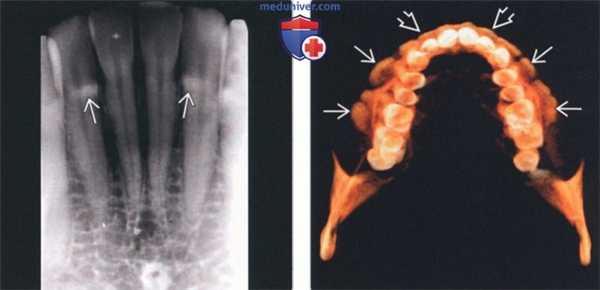

(Слева) На периапикальной рентгенограмме определяются едва заметные рентгеноконтрастные участки возле шеечного края передних зубов. Эти выбухающие участки, чаще возникающие на нижней челюсти, носят название щечной «губы». Клинические они выглядят как маленькие бугорки под нормальной слизистой оболочкой.

(Справа) На аксиальной 3D КЛКТ визуализируются множественные экзостозы с щечной стороны верхней челюсти в области моляров и премоляров. Столь многочисленные экзостозы можно удалить, т.к. они способны привести к функциональным нарушениям. Видна также щечная «губа» в передних отделах верхней челюсти.